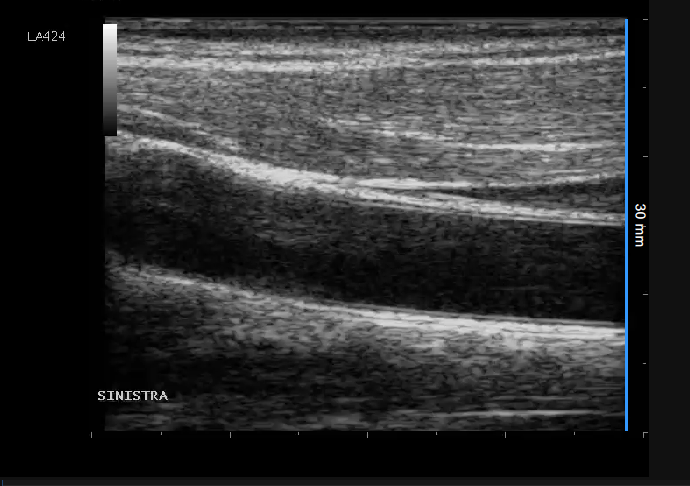

Exemples d'étalonnage en mode B

Les images suivantes présentent des exemples d'étalonnage de l'image en mode B. Les éléments graphiques en rouge indiquent où trouver les informations relatives à la profondeur de l'image échographique.